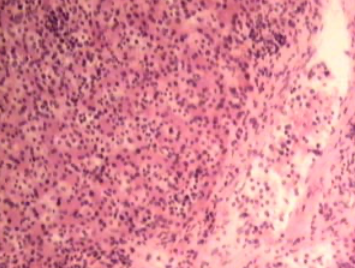

Äge mädane lihasepõletik